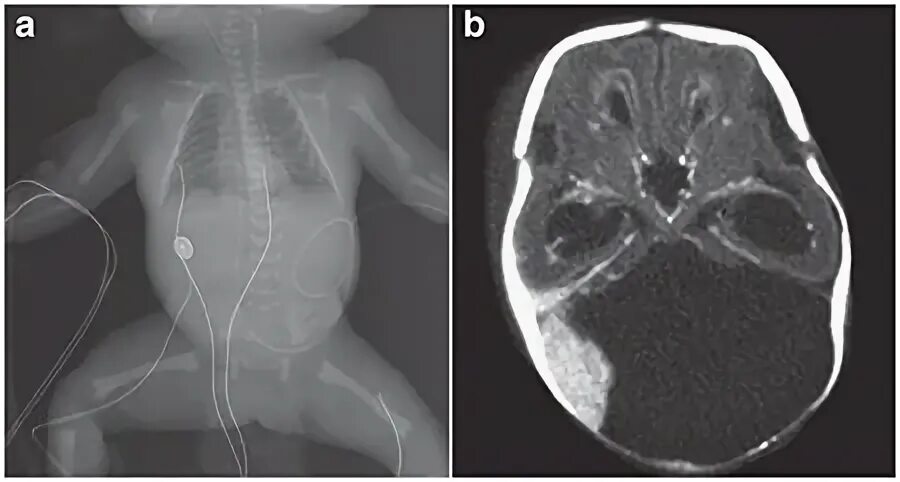

Денди уокера мрт